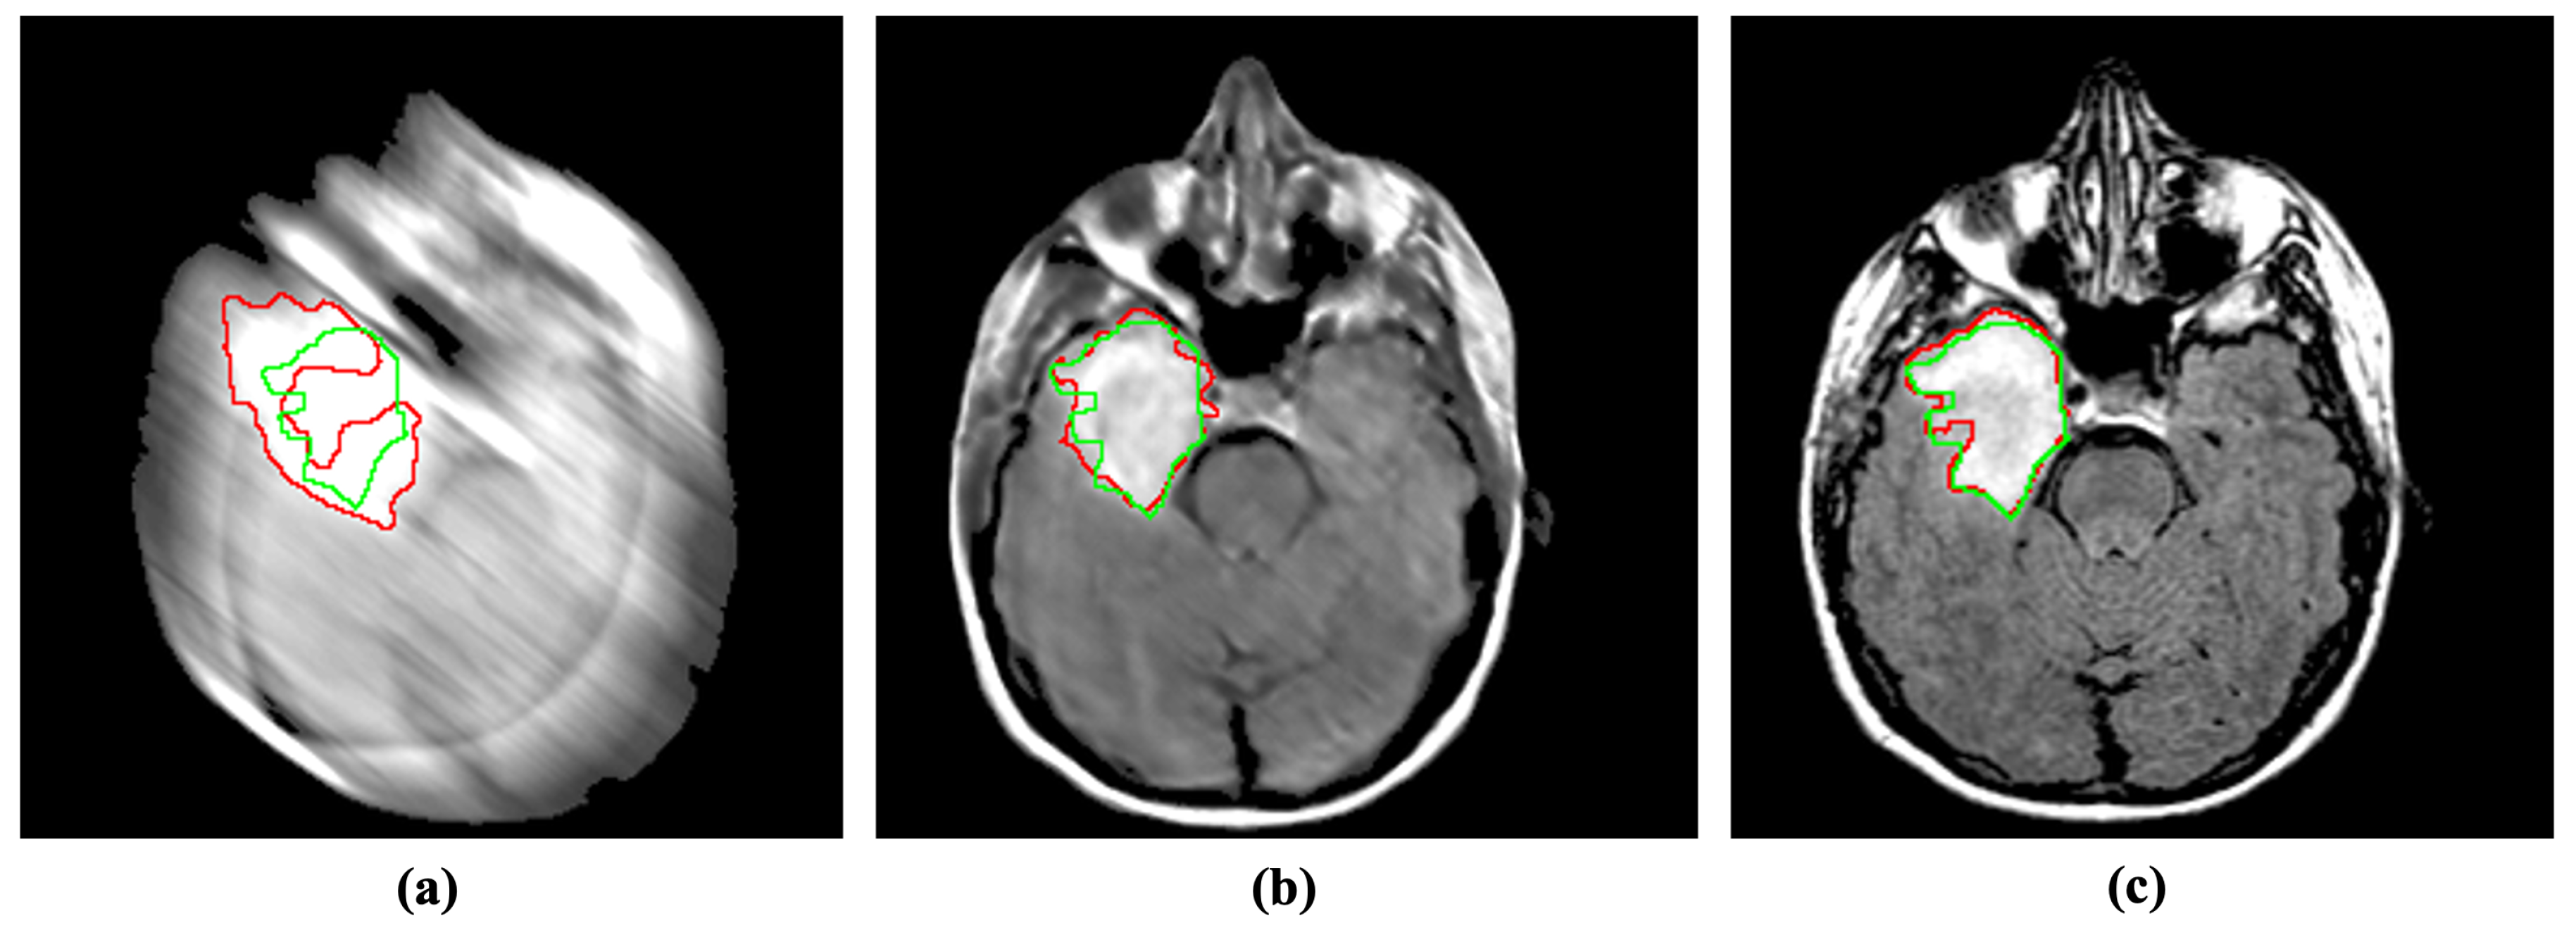

4.2.1. Segmentation

4.2.2. Detection